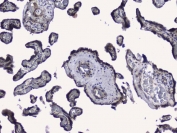

IHC staining of FFPE human placenta with RALBP1 antibody. HIER: boil tissue sections in pH6, 10mM citrate buffer, for 20 min and allow to cool before testing.